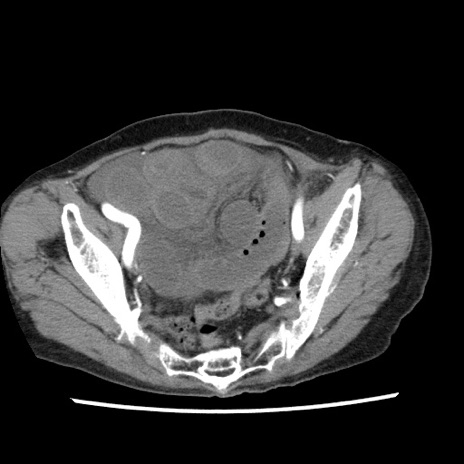

矢状断像